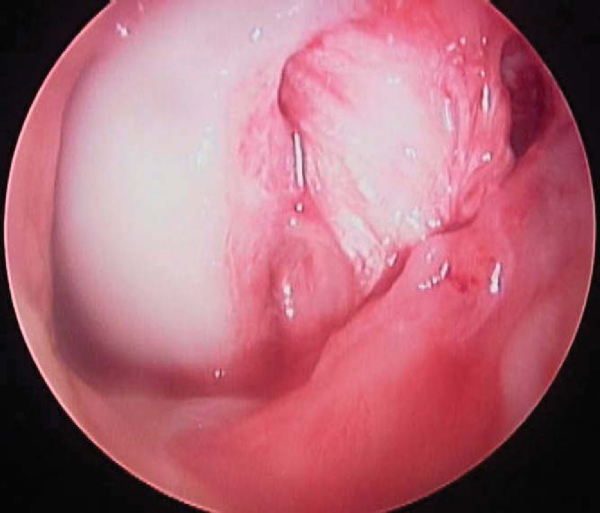

All intraarticular pathology is addressed at this time. The torn PCL may be difficult to recognize until it is viewed completely. An indication of a PCL tear is a “sloppy ACL sign” or ACL pseudolaxity.[6] Once the torn PCL is identified, the PCL stump is débrided, with preservation of any fibers in continuity.